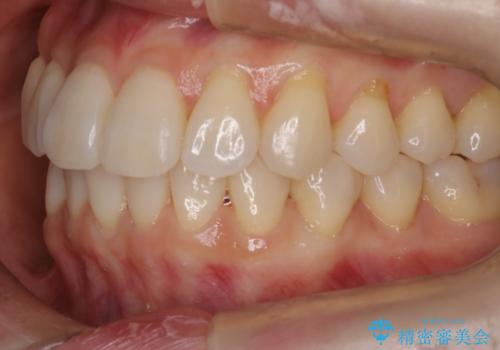

- インビザラインで非抜歯治療を行いました。IPRと拡大をし、叢生、咬合をきれいにしました。

主訴であったかみ合わせを正しい位置に動かし、バランスよくかめるようになりました。矯正治療終了後にメタルインレーをセラミックインレーに替えました。